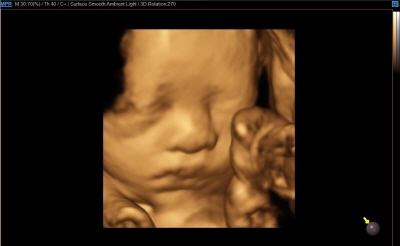

입체 초음파 영상 장비 (삼성 HS50)

초음파 영상에 음영효과를 입혀 입체감 있게 보여주는 기술이 적용된 장비입니다. 태아의 발달과 이상 유무를 자세히 확인하실 수 있습니다.

태아의 초음파 영상은 '세이베베' 서비스를 통해 핸드폰과 PC로 확인하실 수 있습니다.